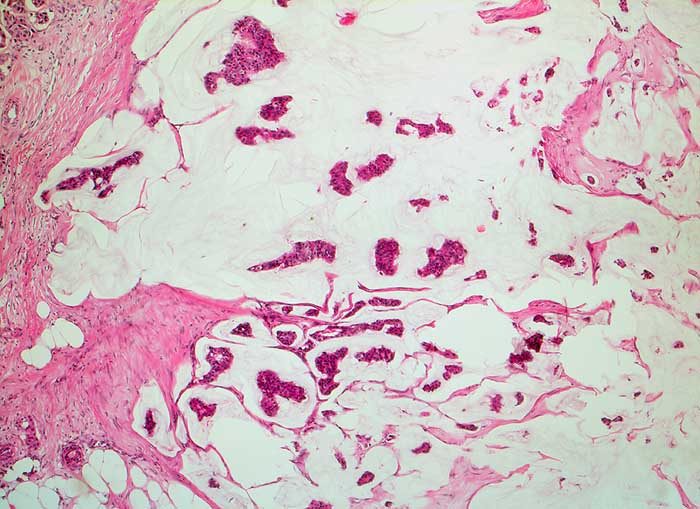

Homogene oder schlierenförmige extrazelluläre Schleimmassen mit Inseln von Tumorzellen mit geringen Kernatypien sind pathognomonisch für das muzinöse Mammakarzinom. Die Zellzahl ist meist nicht sehr hoch. Die Zellen liegen einzeln oder in kleinen kugeligen oder pseudopapillären Verbänden. Der Schleim erscheint in der Pap Färbung blau-grau bis rötlich. Siegelringkarzinome zeigen grössere intrazytoplasmatische Schleimvakuolen.

Unten werden zwei Beispiele von typischen muzinösen Karzinomen gezeigt.